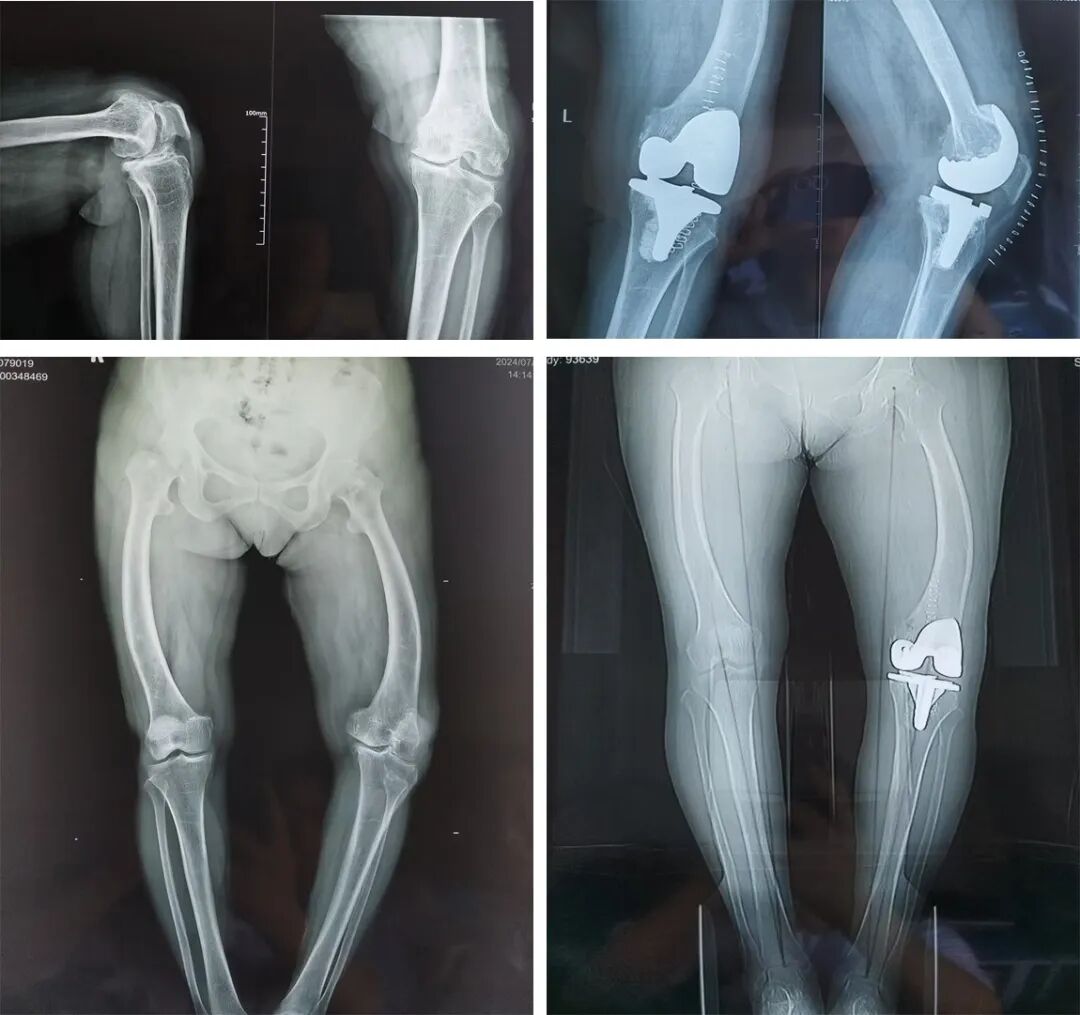

刘阿姨的“膝盖疼”是老毛病了,反反复复折腾了她4年,期间吃药、保守治疗仍然无法解决问题。最近,刘阿姨的左膝盖已经疼到抬不起腿来,这给老人家的身心带来了巨大的痛苦,也造成了生活上的诸多不便。

入院后,经检查诊断刘阿姨为膝关节骨性关节炎伴有股骨畸形,合并高血压病2级。为了彻底解决刘阿姨的病痛,外二科张同顺主任及其手术团队反复推敲之后决定为其行“左侧人工全膝关节置换术”。

由于患者左膝关节及左股骨严重畸形,手术难度很高,张主任凭借丰富的经验和过硬的技术与其团队缜密配合,左膝人工全膝关节置换术顺利完成。